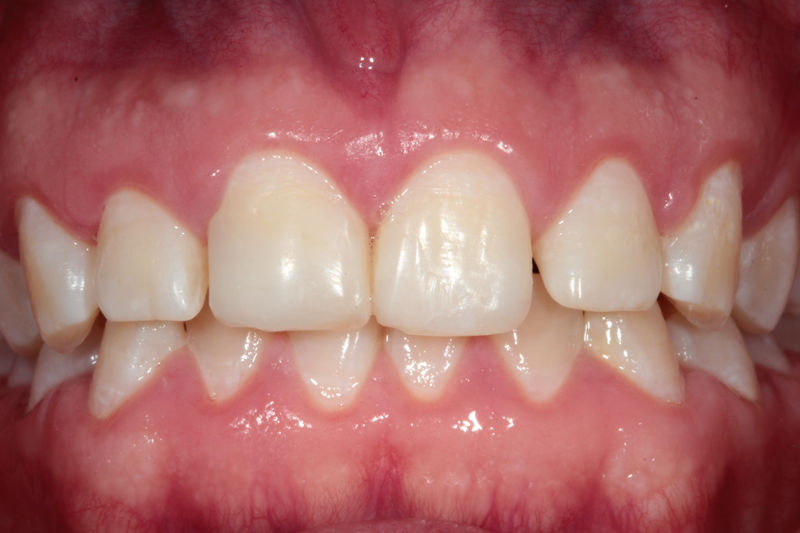

Implantes, ortodoncia y coronas.